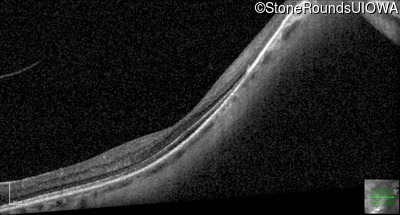

Infrared Fundus Photograph - Left - 20/25 +2

Exemplar